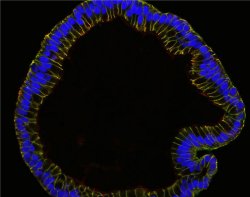

Partindo de células-tronco, a equipe fez com que elas se desenvolvessem até formar a camada mais interna das trompas de Falópio, incluindo uma membrana equivalente ao epitélio mucoso, com suas pregas e projeções.

As células-tronco transformaram-se não apenas nos tipos de células que ocorrem na camada da mucosa, mas também desenvolveram características do órgão como um todo, por exemplo, a sua arquitetura característica.